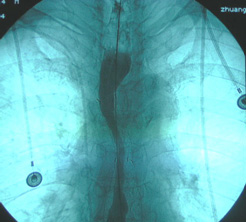

對疑有食管癌的病例可用以下方法確診:①拉網法採取食管上皮細胞作塗片,進行細胞學檢查,診斷正確率87~96%。②X射線鋇餐造影,診斷正確率可達96%左右。③食管鏡檢查可以直接觀察食管黏膜,結合活檢,對食管癌尤其是早期癌的診斷和定位是最可靠的方法。鑑別診斷需與食管功能性吞咽困難、良性狹窄、外壓性食管梗阻、良性腫瘤、賁門失弛緩、食管憩室、食管結核等疾病相鑑別。